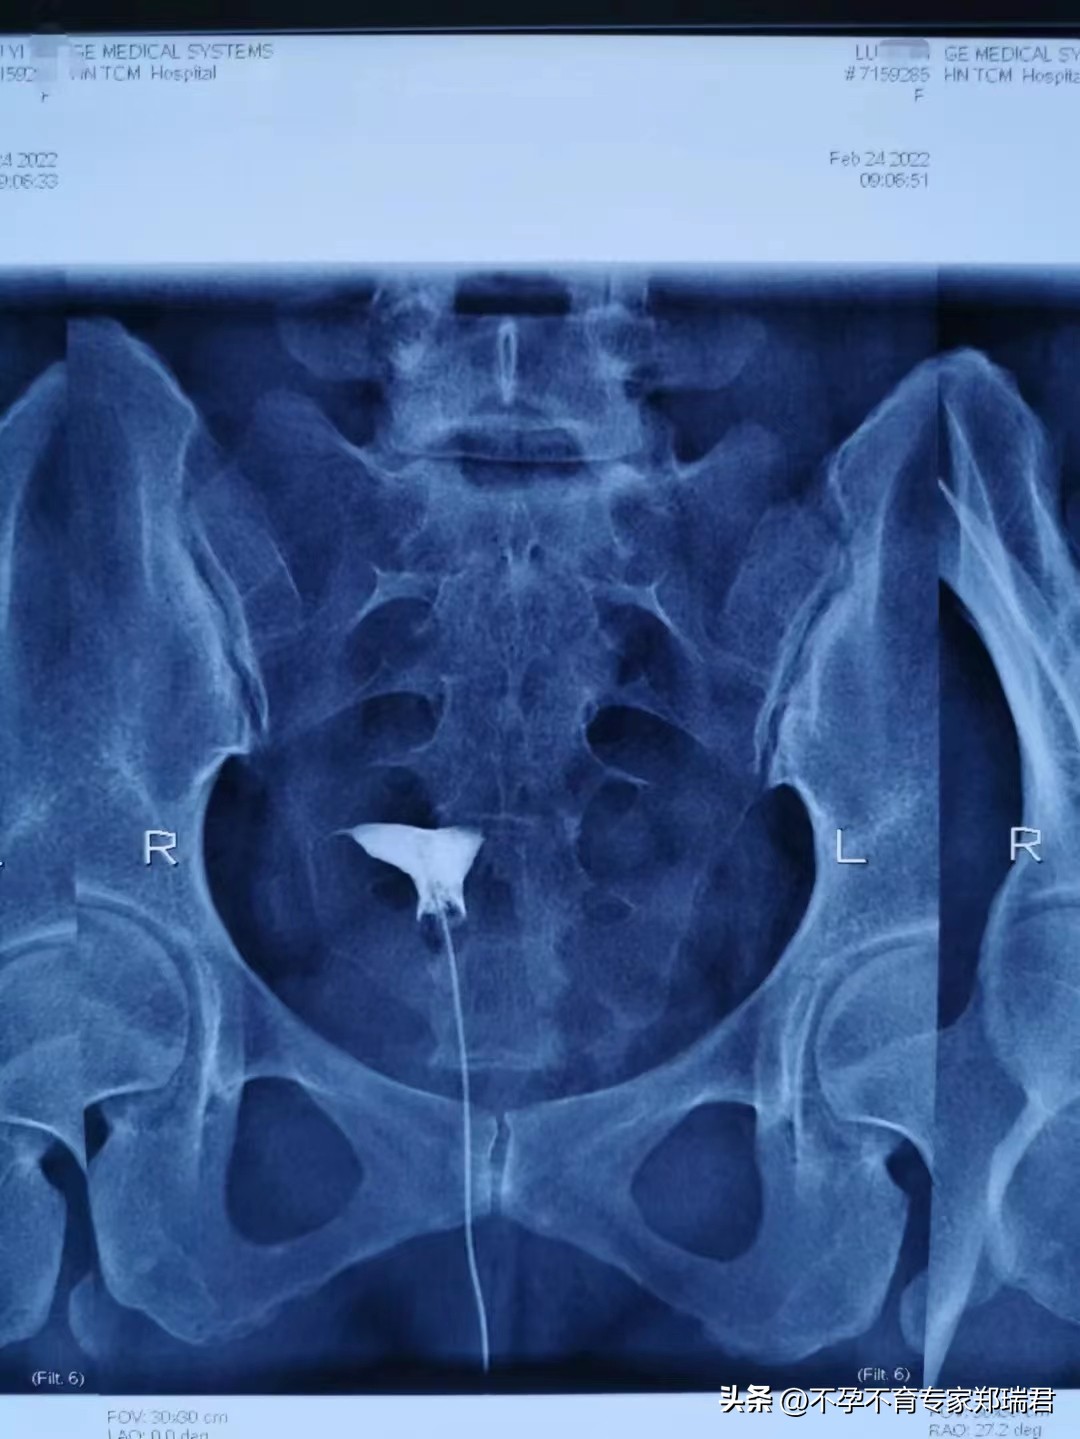

2022年2月24日子宫输卵管造影检查结果回示:

双侧输卵管不通!!

具体为:

宫体右偏;

右侧输卵管峡部近端显影梗阻;

左宫角轻度充盈缺损,左侧输卵管间质部梗阻。